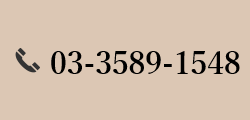

舌側矯正(裏側矯正)

舌側矯正とは、歯の裏側に装置を取り付ける矯正治療で、裏側矯正とも呼ばれます。口を開けたときに装置が見えないため、周りの人に気づかれにくいことが特徴です。職業上、目立つ装置を使用できない方に向いています。なお、裏側矯正を適切に行うには、高度なスキルが必要です。

舌側矯正とは、歯の裏側に装置を取り付ける矯正治療で、裏側矯正とも呼ばれます。口を開けたときに装置が見えないため、周りの人に気づかれにくいことが特徴です。職業上、目立つ装置を使用できない方に向いています。なお、裏側矯正を適切に行うには、高度なスキルが必要です。